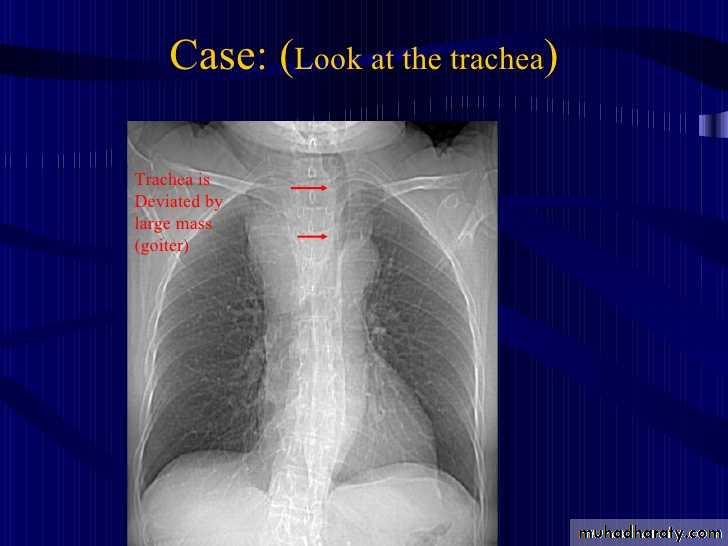

Retrosternal Goiter

What is the main difference between 2 films ??? What is the shape of each one ??? A. B.

Emphysema

25.retrosternal Goiter

26.retrosternal Goiter